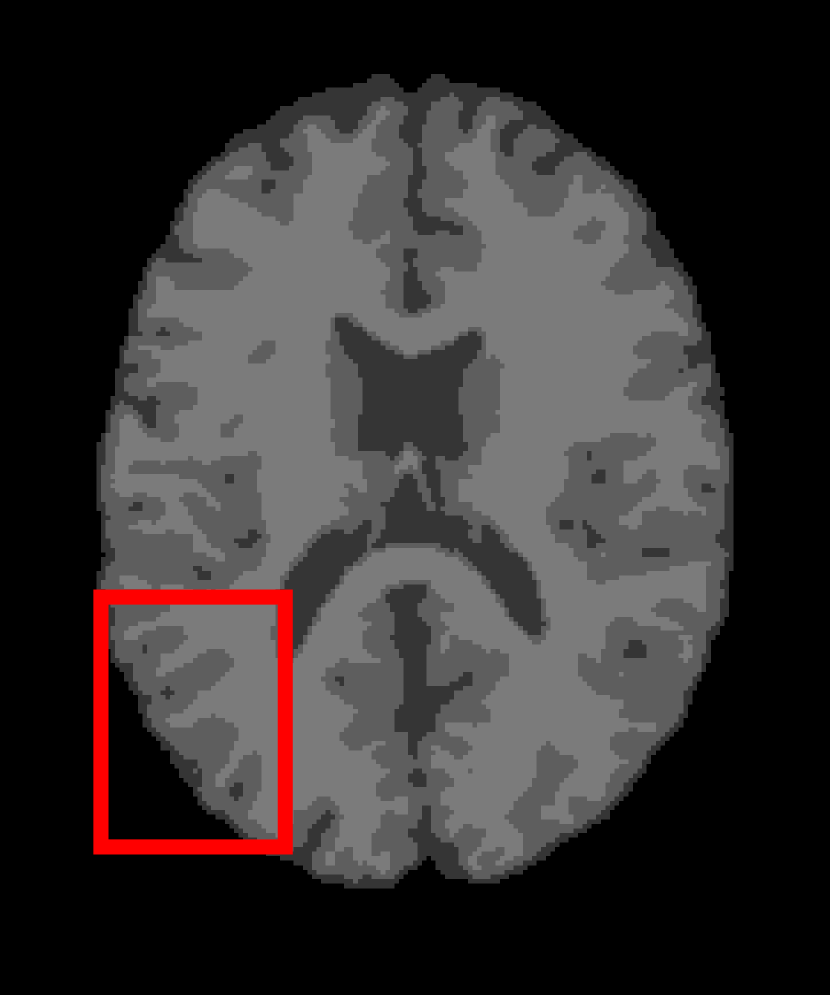

Next, we representatively segment five medical images from BrianWeb. They are represented as five slices in the axial plane with a sequence of 70, 80, 90, 100 and 110, which are generated by T1 modality with slice thickness of 1mm resolution, 9% noise and 20% intensity non-uniformity. Here, we set c=4𝑐4c=4 for all cases. The comparison between WRFCM and its peers are shown in Fig. 9 and Table II. The best values are in bold.

Figure 9: Segmentation results on five medical images. The parameter: ϕ=5.35italic-ϕ5.35\phi=5.35. From top to bottom: noisy images, ground truth, and results of FCM_S1, FCM_S2, FLICM, KWFLICM, FRFCM, WFCM, DSFCM_N, and WRFCM.

By a view of the marked red square in Fig. 9, we find that FCM_S1, FCM_S2, FLICM, KWFLICM and DSFCM_N are vulnerable to noise and intensity non-uniformity. They give rise to the change of topological shapes to some extent. Unlike them, FRFCM and WFCM achieve sufficient noise removal. However, they produce overly smooth contours. Compared with its seven peers, WRFCM can not only suppress noise adequately but also acquire accurate contours. Moreover, it yields the visual result closer to ground truth than its peers. As Table II shows, WRFCM obtains optimal SA, SDS and MCC results for all five medical images. As a conclusion, it outperforms its peers visually and quantitatively.